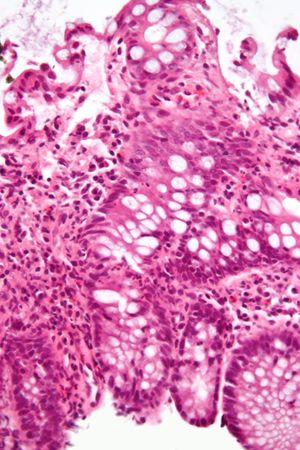

| ميكروگراف يـُظهـِر cryptitis, a ارتباط مجهري لالتهاب القولون. H&E stain. | |